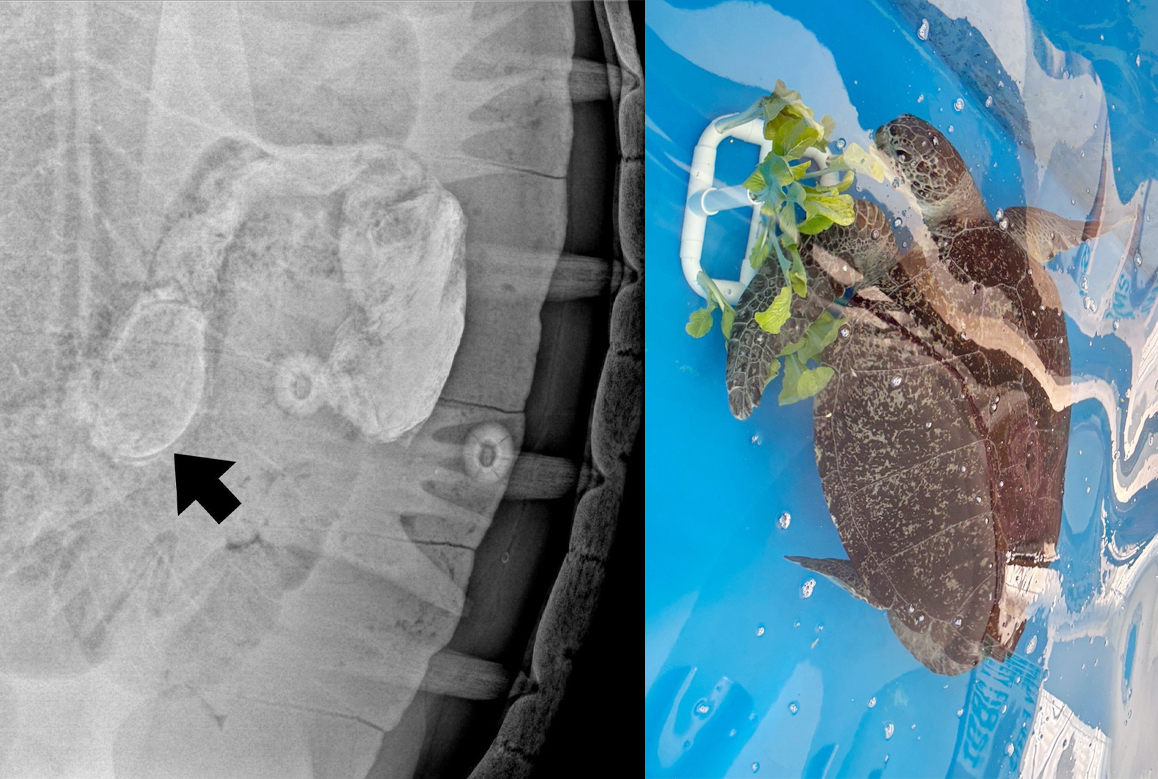

Veterinarians at the Siritharn Rare Marine Animal Rescue Center conducted continuous monitoring and diagnostic tests after the turtle’s admission. X-ray imaging with barium contrast on December 1 detected the wristband in the animal’s digestive tract.

Officials said the wristband, measuring about 20 centimeters in circumference, was mixed with fecal matter but did not cause an intestinal blockage. Blood test results remained within normal ranges, and the turtle was able to eat and excrete normally.

After daily health assessments, veterinarians confirmed that the turtle successfully passed the yellow wristband on December 18, along with banana leaves. The entire process, from ingestion to excretion, took 27 days.